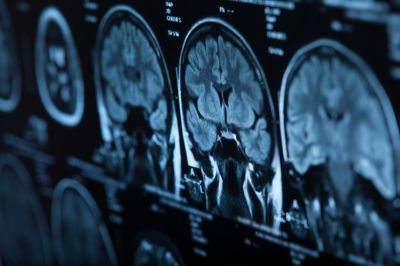

Длительное воздействие загрязненного воздуха связано с повышенным риском развития менингиомы — распространенной опухоли головного мозга. Предположительно, очищение воздуха может помочь снизить заболеваемость.

Фото: 123rf.com